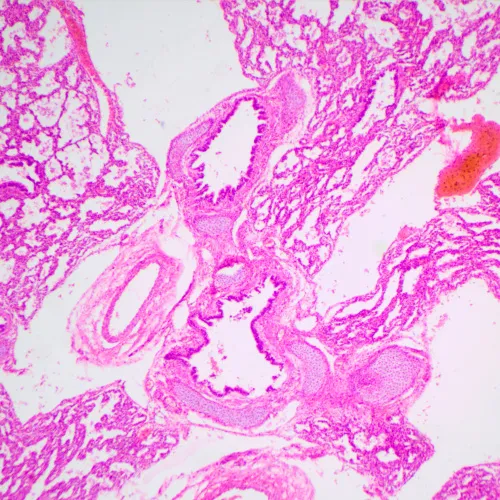

MAGUS Bio 240T е малък биологичен микроскоп за обучение и изследователски цели. Предназначен е за работа с прозрачни и полупрозрачни биологични образци по метода на светлото поле. Микроскопът има кодирана револверна глава, която поддържа избрания интензитет на светлината за всеки от обективите, и екран с течнокристален дисплей, на който се показват работните параметри.

• Работи с прозрачни и полупрозрачни биологични образци по метода на светлото поле